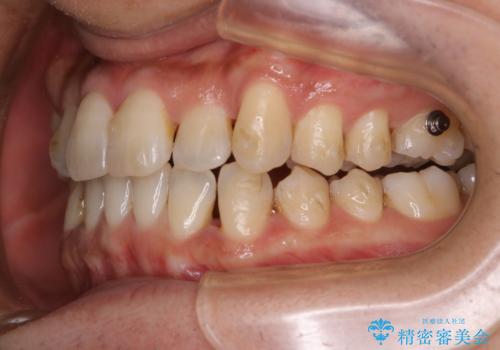

マウスピース矯正インビザライン治療では、歯の表面にアタッチメントという突起を設定します。(アタッチメントは歯の動きを効率的に移動するためのものです)

アタッチメントが歯に付くと、表面が凸凹し磨き残しが多くなったりと、プラークや歯石・着色がつきやすくなることがあります。

矯正治療中もPMTCを定期的に行い、専門的な機械でしっかりと汚れを除去することがおススメです。